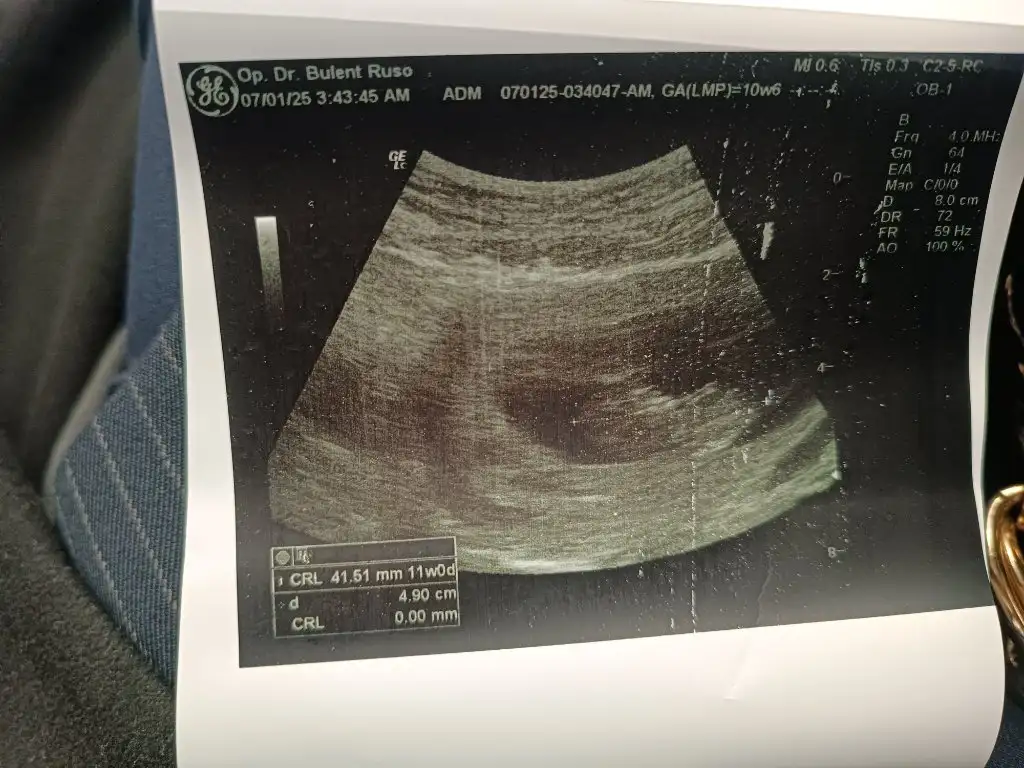

Kızlar hayırlı bereketli cumalar olsun inşallah. Az evvel doktordan geldim ense kalınlığı 2.2 dedi üçe kadar normal sayılabilir ama buda biraz yüksek dedi burun kemiği görünüyo dedi fetal DNA önerdi. Şuan 12+1 im ultrason fotoğrafını atıyorum şimdi hem fikir hemde cinsiyet tahmini almak istiyorum sizlerden,

Eklentiler

• 17358965762895763360544556751194.webp

45,1 KB · Görüntüleme: 115